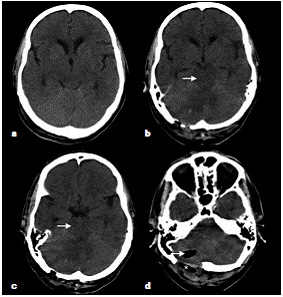

En la tomografía computadorizada de control se observó persistencia de la hipodensidad de la región mesencefálica, así como cambios por la craniectomía suboccipital y el drenaje del hematoma cerebeloso derecho (figura 2). Debido a la persistencia del deterioro clínico, se hizo una resonancia magnética en la cual se encontraron múltiples eventos isquémicos (edema citotóxico) que afectaban especialmente los territorios de ambas arterias cerebrales posteriores y de la arteria cerebral media, y el territorio limítrofe profundo de dichas arterias; la hipodensidad tomográfica en el mesencéfalo y en el puente correspondía a edema vasogénico (figura 3).

Se decidió tomar imágenes de las lesiones por resonancia magnética, en las cuales se evidenció un aumento de las zonas isquémicas en ambas arterias cerebrales posteriores y en la arteria cerebral media, así como en el territorio limítrofe profundo de esta, además de edema vasogénico que se extendía hasta la región del núcleo basal, la mesencefálica y el tallo cerebral, y la sustancia blanca profunda de los hemisferios cerebelosos (figura 4).